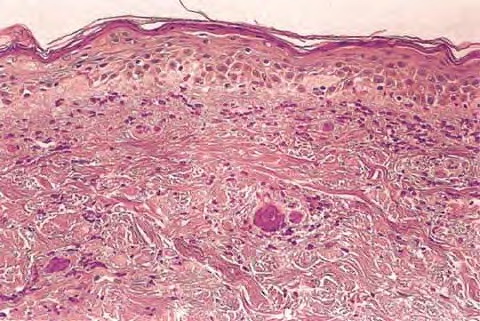

Nevus verrucosus = وحمة ثؤلولية